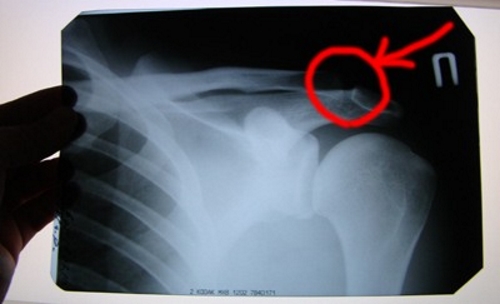

Рентгенография помогает исключить вывихи и переломы, а МРТ, хотя назначается реже, позволяет оценить степень повреждения мягких тканей. Артроскопия может потребоваться при повреждении суставной капсулы и наличии кровотечений.